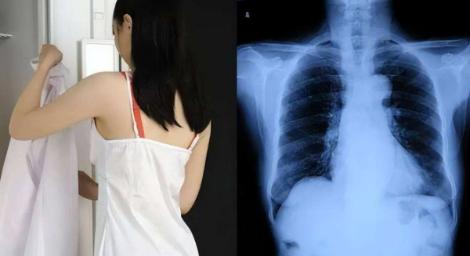

妹子照X光!男醫生提要求「上衣脫光光」 她火大投訴…醫院這樣說

·

2022/06/23